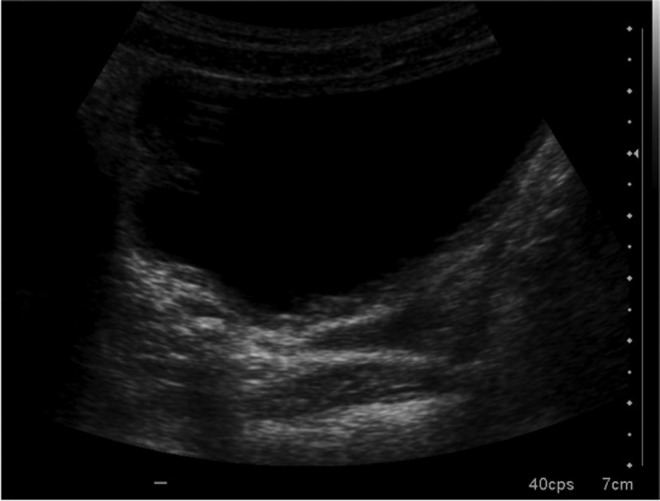

During a routine checkup using ultrasonography, a right ureteral pyelocaliceal ectasia was identified (Fig. 1), which had already been seen in earlier checkups. Inside the dilated right ureter, an echogenic focus with shadowing was identified. KUB showed a calcium density, which measured 4.2 × 4.4 mm in the right pelvic area. This was not seen in earlier checkups. Microureteroscopy was performed using a MicroPerc set 4.8F sheath, optic diameter of 0.9 mm, and standard gravity irrigation.

FIG. 1.

Ultrasonography in which a hyperechoic area is detected on the right distal ureter.